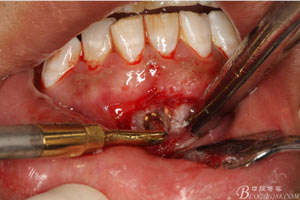

圖9.清晰可見(jiàn)牙膠從31根尖1/3溢出。

圖10.從唇側(cè)側(cè)穿除切除31根尖部分。